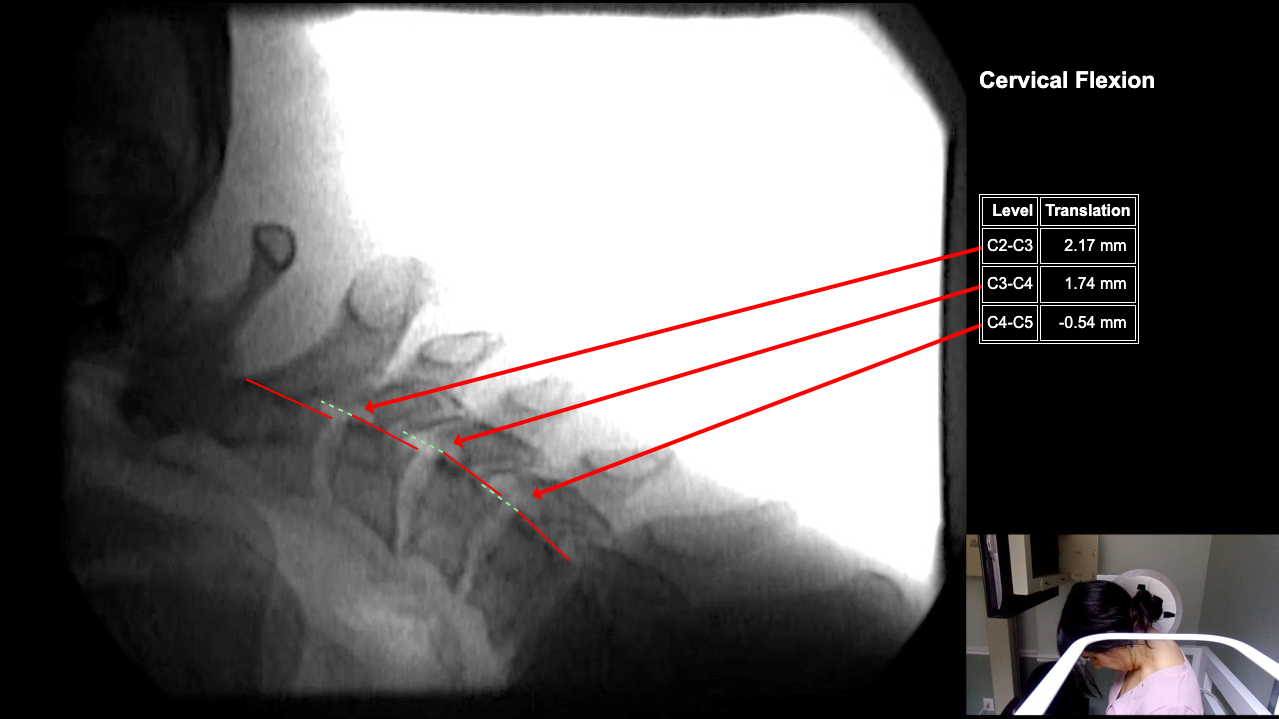

Image 2